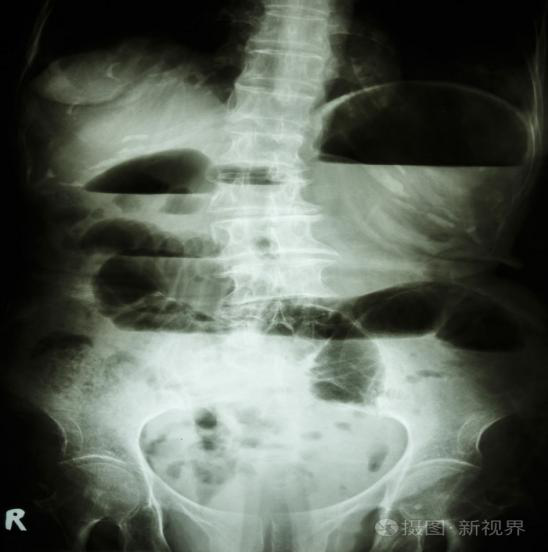

圖示:腸梗阻患者,可見腹部腸管擴張,并伴有大量高低不等的氣液平面,這是腸梗阻的典型表現。